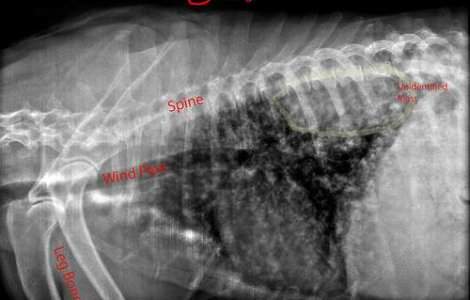

O femeie din Olanda a ajuns la spital cu dureri severe de stomac, iar razele X au relevat cauza: 78 de linguri si furculite.